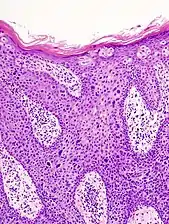

Histopathologically, the epidermis in cSCC in situ (Bowen's disease) will show hyperkeratosis and parakeratosis. There will also be marked acanthosis with elongation and thickening of the rete ridges. These changes will overly keratinocytic cells which are often highly atypical and may in fact have a more unusual appearance than invasive cSCC. The atypia spans the full thickness of the epidermis, with the keratinocytes demonstrating intense mitotic activity, pleomorphism, and greatly enlarged nuclei. They will also show a loss of maturity and polarity, giving the epidermis a disordered or "windblown" appearance.

Two types of multinucleated cells may be seen: the first will present as a multinucleated giant cell, and the second will appear as a dyskeratotic cell engulfed in the cytoplasm of a keratinocyte. Occasionally, cells of the upper epidermis will undergo vacuolization, demonstrating an abundant and strongly eosinophilic cytoplasm. There may be a mild to moderate lymphohistiocytic infiltrate detected in the upper dermis.[12]

Bowen's disease is essentially equivalent to and used interchangeably with cSCC in situ, when not having invaded through the basement membrane.[12] Depending on source, it is classified as precancerous[13] or cSCC in situ (technically cancerous but non-invasive).[47][48] In cSCC in situ (Bowen's disease), atypical squamous cells proliferate through the whole thickness of the epidermis.[12] The entire tumor is confined to the epidermis and does not invade into the dermis.[12] The cells are often highly atypical under the microscope, and may in fact look more unusual than the cells of some invasive squamous-cell carcinomas.[12]